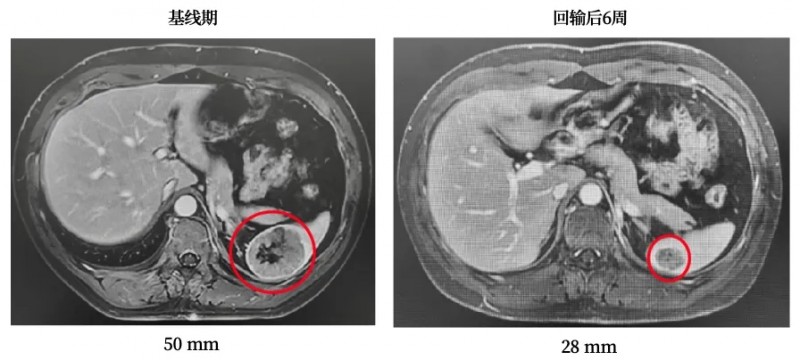

奇迹,在悄然间降临。2022 年 10 月,TIL 回输后仅仅 6 周,复查影像显示,他胰头部位的复发病灶竟快速缩小至 3 厘米,残余的肝转移病灶更是消失得无影无踪。不仅如此,多个原本居高不下的肿瘤标记物也奇迹般地恢复至正常水平。此后的每一次复查,他的肿瘤病灶都在不断缩小,直至丧失代谢活性。